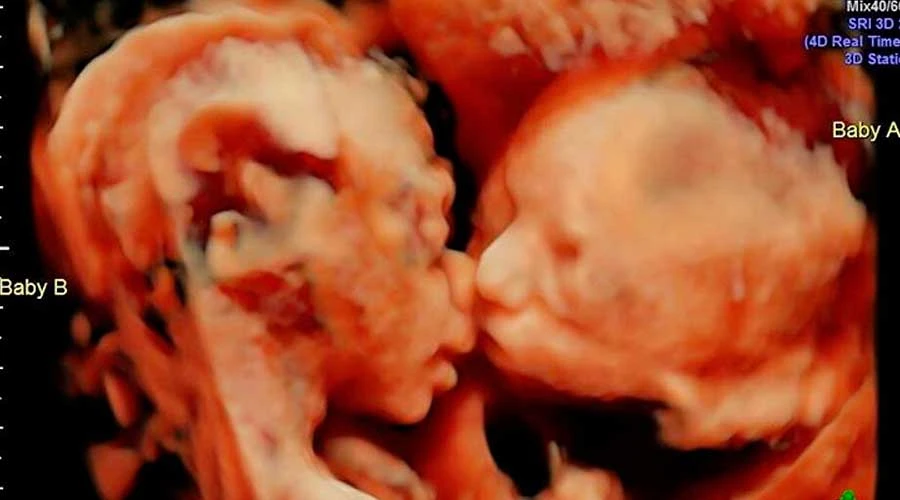

Melisa y Jaime son dos padres invidentes que quedaron conmovidos cuando su médico, Jezid Miranda, les entregó uno de los más grandes regalos que podían recibir: una ecografía en alto relieve de su hijo que nacerá a finales de octubre.

Ambos viven en Cartagena, en el norte de Colombia, y recibieron la ecografía en uno de los controles prenatales. "Para que tengas ese vínculo con tu bebé, hemos hecho con mucho cariño esta imagen de tu bebé", le dijo el médico a Melissa.

El cuadro con la imagen incluye una leyenda en braille con el nombre del bebé y la información sobre su salud.

En su cuenta de Twitter, Miranda escribió que "aunque Melisa y Jaime son invidentes desde la infancia, nunca dejaron que eso les impidiera cumplir sus sueños y están esperando a su bebé".

"Deseamos que nuestro regalo, una impresión 3D de la cara de su bebé, pueda ayudarlos a unir su corazón hasta que puedan tocarlo al nacer", expresó.

En declaraciones a Noticias Caracol, la madre relató que "cuando me la entregaron, casi no podía hablar. Lloré, fue mucha la emoción porque realmente no me lo esperaba. Así, tan detallado, como tan real".

Por su parte, Jaime también manifestó su alegría y dijo que aunque no puede ver la imagen de su bebé, "sé que es hermoso, y que es una impresión espectacular poder tocar por primera vez, yo, o sentir el rostro de mi hijo con el tacto".